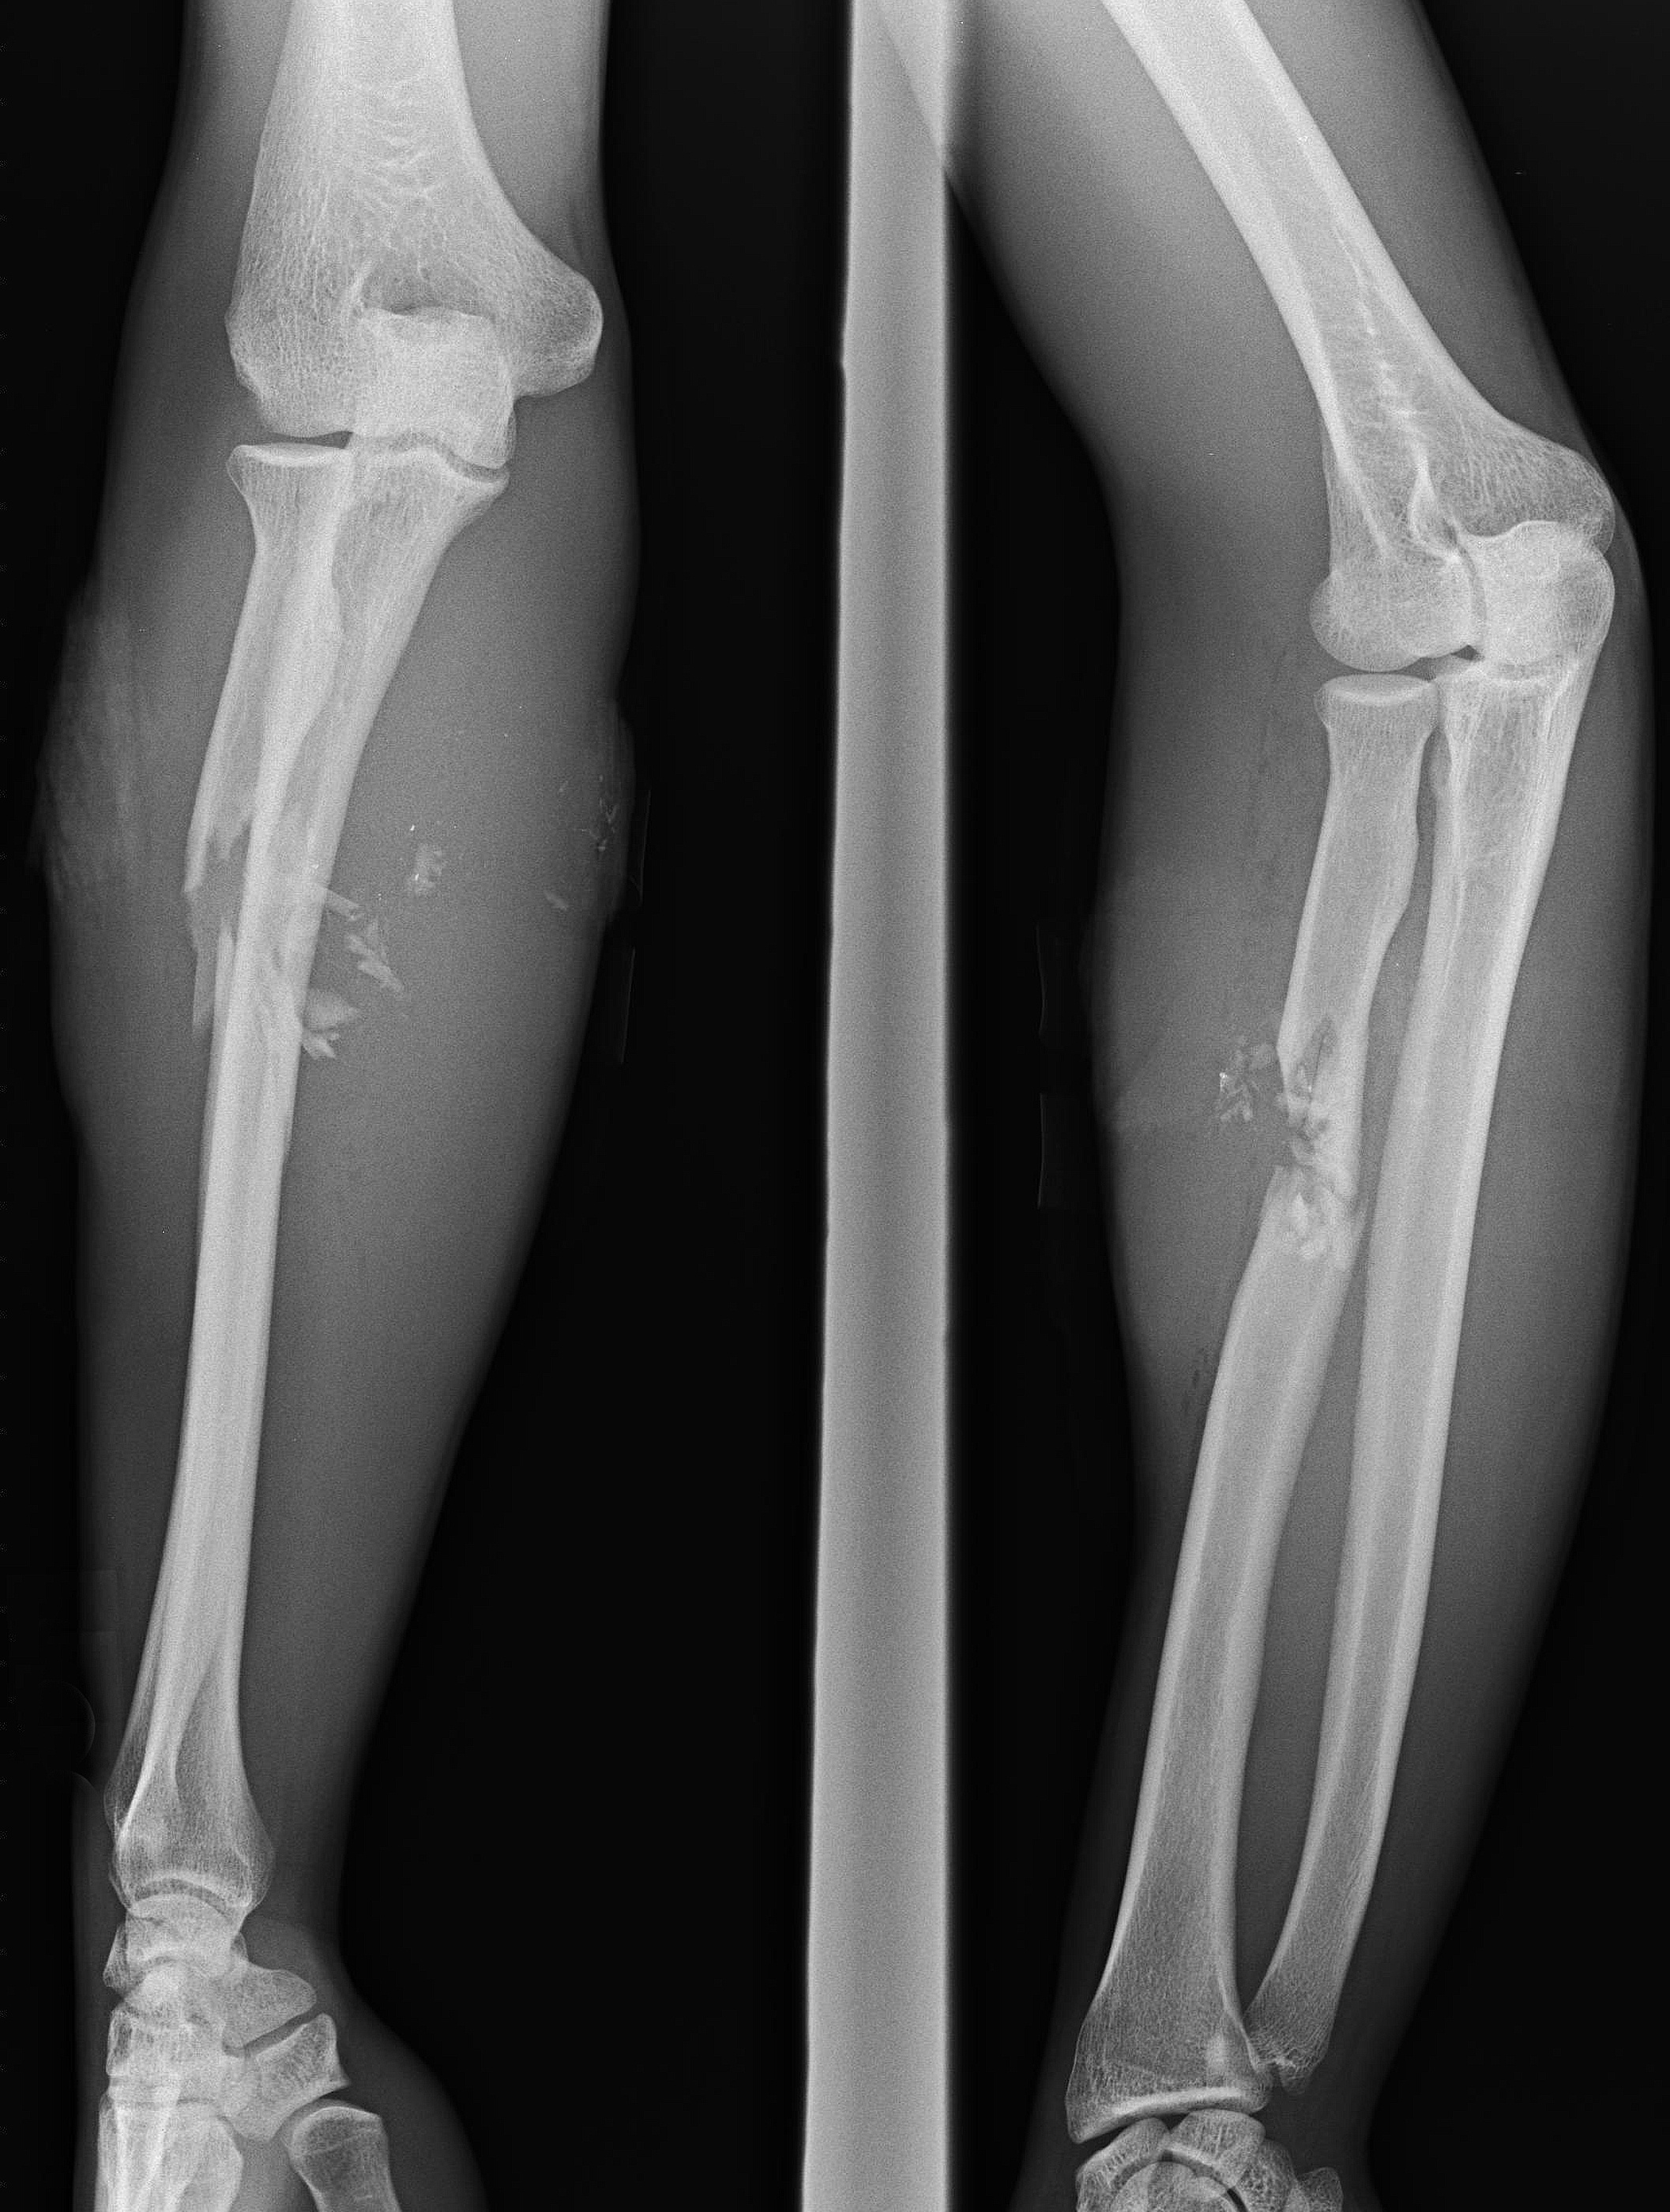

Wichtig: Anhaltende Schmerzen nach Verletzungen und Unfällen müssen ärztlich abgeklärt werden! Calcium phosphoricum Einzelmittel Calcium phosphoricum Leitsymptome • ältere Brüche, die nur langsam verheilen oder schlecht zusammenwachsen• dabei immer wieder Schmerzen an kleiner, umschriebener Stelle Stimmung — Verbesserung — Verschlechterung • Wetterwechsel• kaltes Wetter Potenz D 6 Einnahme 3-mal täglich 5 Globuli bis zur Besserung, dann Abstände verlängern bis zum Abklingen der Beschwerden. Symphytum Einzelmittel Symphytum Leitsymptome • bei Knochenbrüchen und Verletzungen der Knochenhaut• starke stechende Schmerzen, sowohl akut als auch bei schon verheilten Brüchen• fördert die Kallusbildung und die Neubildung von Knochengewebe• auch bei schmerzhafter Knochenprellung (Verletzung der Knochenhaut)• „Schneeballsyndrom“, […]